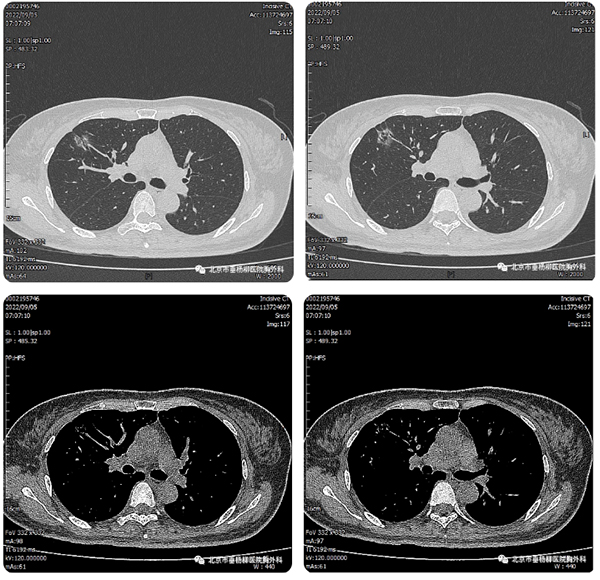

【垂医科普】电视胸腔镜下右肺上叶前段切…